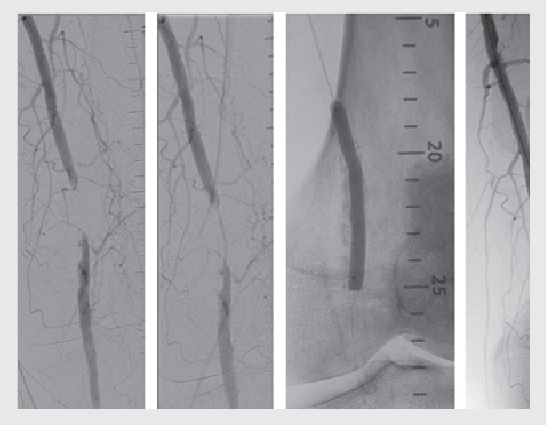

3. Angioplasty and stenting: In some cases, minimally invasive procedures like angioplasty (using a balloon to widen the artery) and stent placement (to keep the artery open) may be performed to improve blood flow.